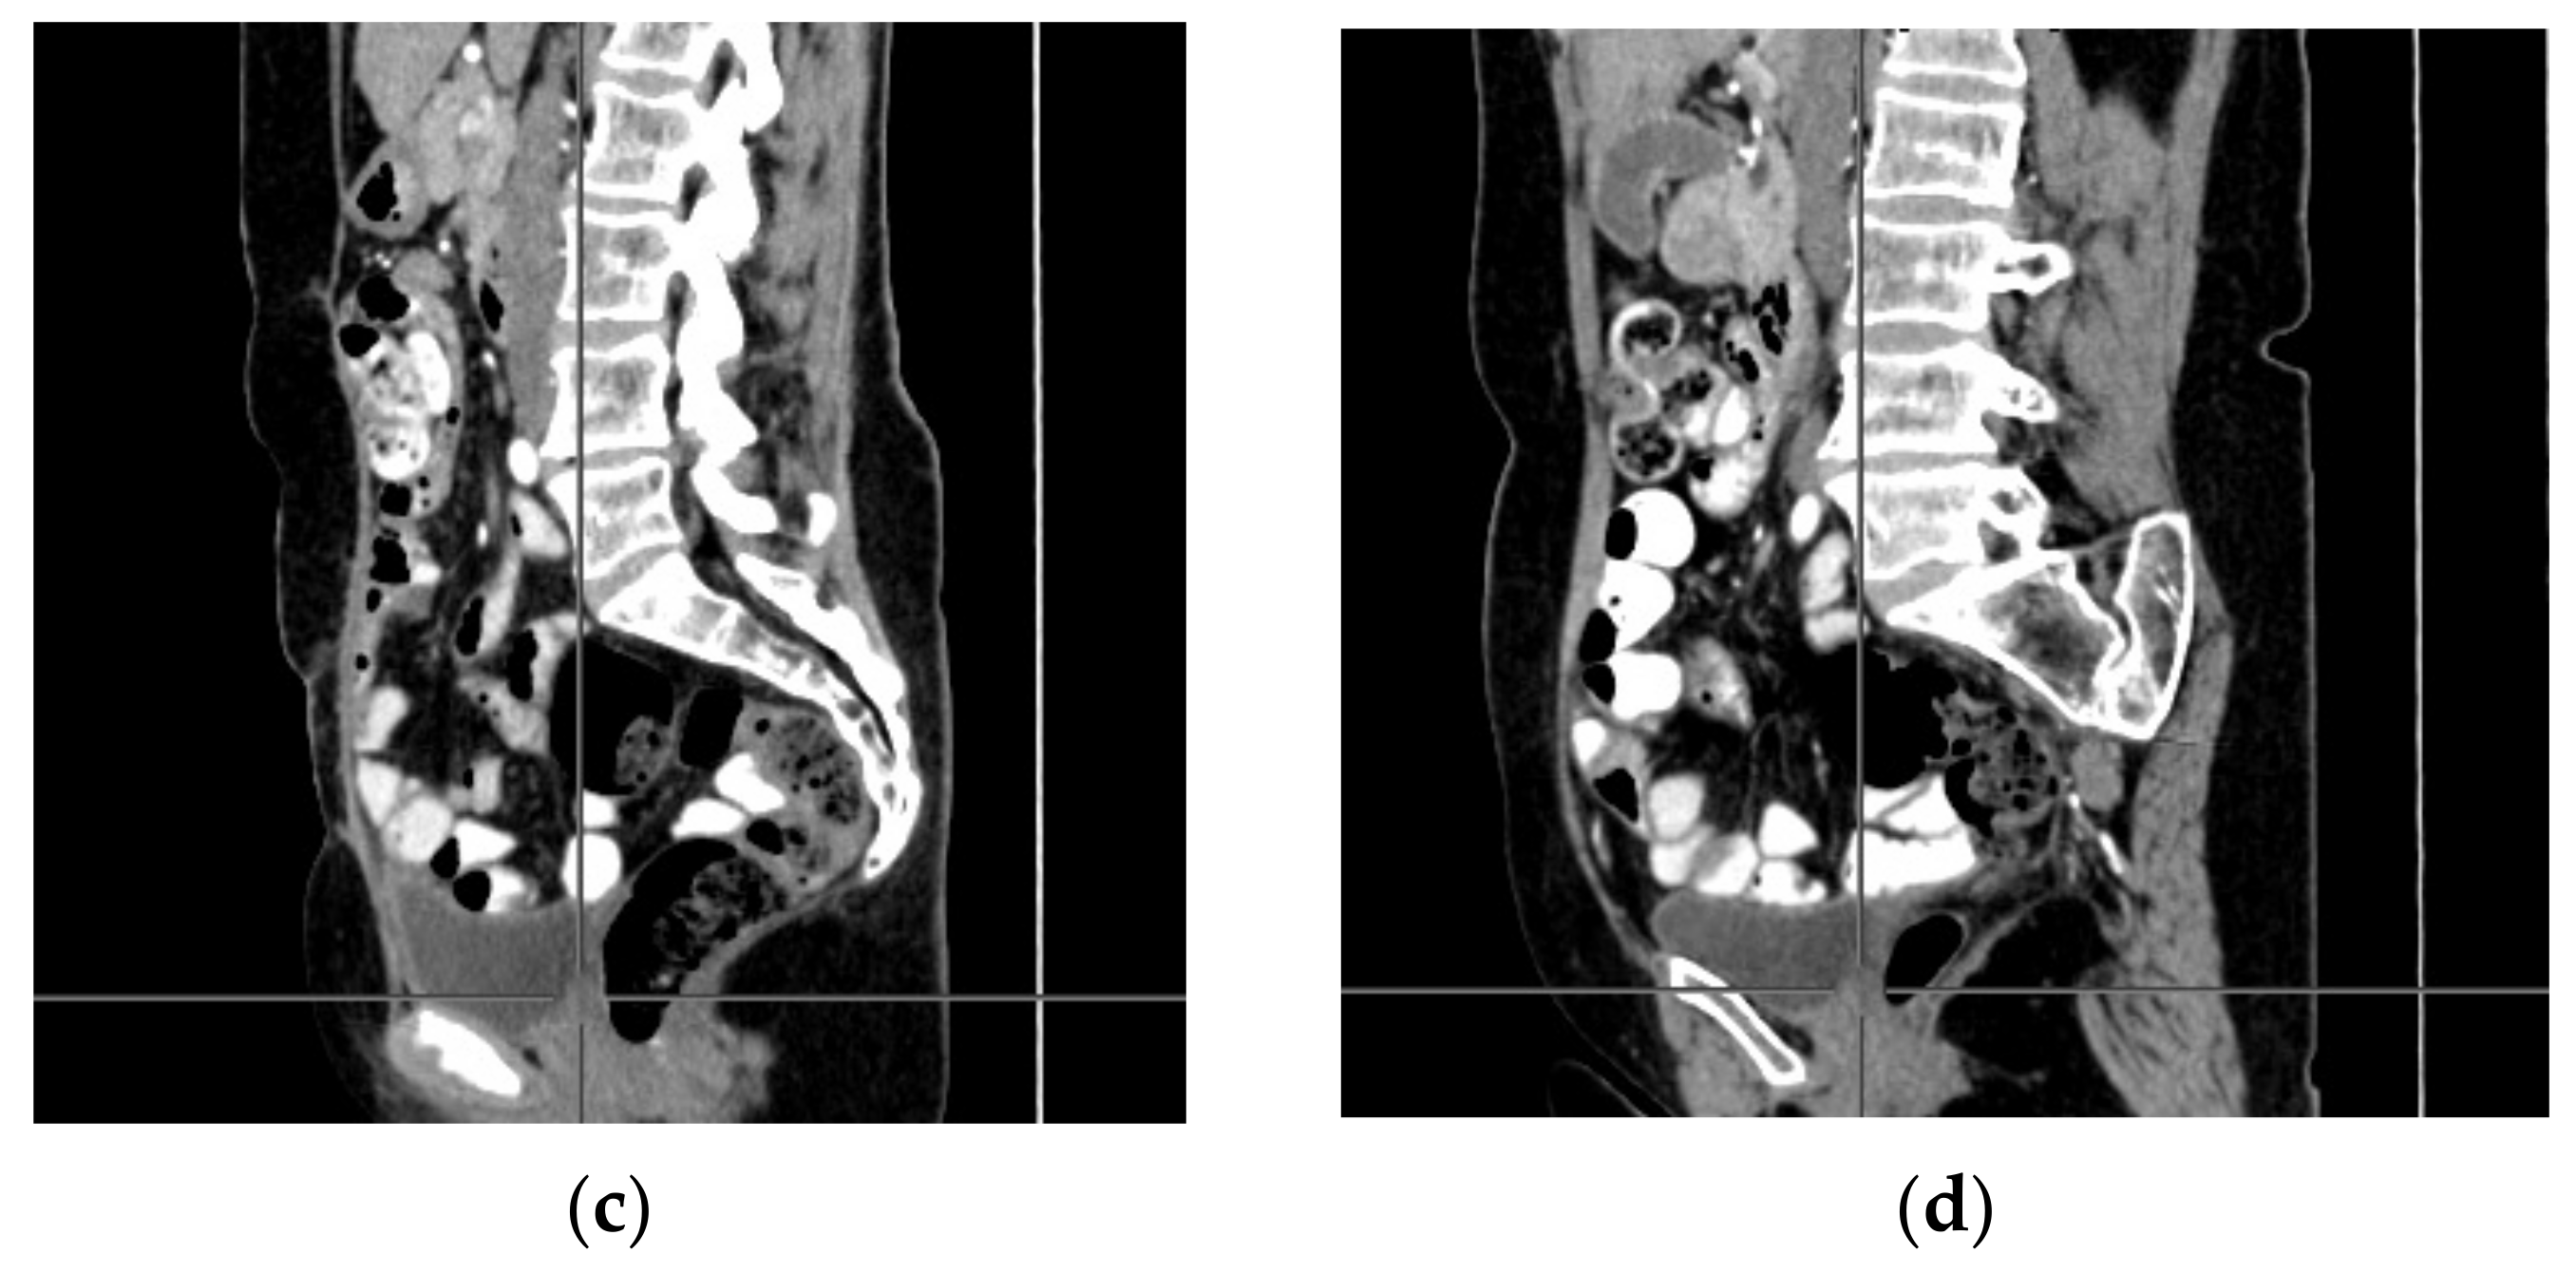

2. Case Report